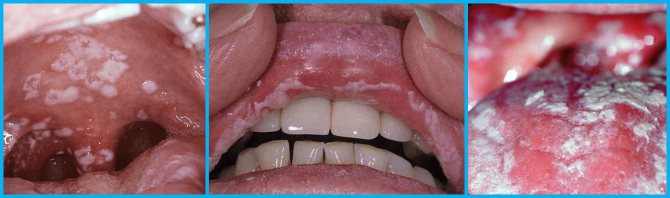

- Кандидозный стоматит или молочница ротовой полости — одно из основных заболеваний, при котором во рту появляются белые пятна и налет. Его появление чаще всего бывает связано с ослаблением иммунитета, благодаря чему его возбудитель — грибок Candida — начинает активно размножаться в полости рта. Белые пятна в этом случае напоминают творожистый налет, обильно покрывающий слизистую. При попытках его устранить обнажаются многочисленные очаги воспаления, а в последствии и эрозии.

- Афтозный стоматит. Может быть вызван вирусными или бактериальными инфекциями, аллергическими реакциями, болезнями ЖКТ или даже гормональным дисбалансом в организме. Сопровождается появлением во рту круглых белых бляшек с красными ободками, которые без надлежащего лечения могут превратиться в серьезные язвы.

- Лейкоплакия. Заболевание такого рода предполагает появление ороговевших участков на слизистой оболочке десен в виде твердых белых или серых бляшек. Подобная патология может быть связана с механическими или термическими повреждениями тканей (неправильно поставленная пломба, чрезмерно горячая пища и т. д.) или табакокурением.

- Молочница (кандидоз). Белые пятнышки локализуются на корне и его краях, в запущенных случаях могут полностью покрыть весь язык, а далее – всю полость рта. При попытке соскабливания такого налета под ним открывается яркая кровоточащая язва. Виновница – грибковая инфекция, возникающая при общем снижении иммунитета организма. Особенно подвержены кандидозу люди пожилого возраста и инфицированные ВИЧ.

По тому, где именно в ротовой полости расположены белые точки и пятна, можно сделать предварительный вывод о том, какое заболевание послужило причиной их появления, например, при кандидозном стоматите они покрывают щеки, язык и небо, при лейкоплакии — десны, а у больных тонзиллитом сосредоточены преимущественно на миндалинах.

Белые болячки во рту, как правило, симптом стоматита – инфекционного недуга, атакующего организм со сниженным иммунитетом. То, какие появятся пятна на небе во рту, обуславливается видом и формой (острой, хронической) заболевания.

- афтозным (множественные белые болячки на ротовой слизистой, болезненные язвы с четко очерченными границами);

- герпетиформным (слизистая обильно усыпана болезненными зудящими пятнышками, которые визуально похожи на герпес, чаще всего болезнь поражает представительниц слабого пола в возрасте до 30 лет);

- грибковым (на мягких тканях присутствует белый налет, возбудитель, как правило, грибок Кандида);